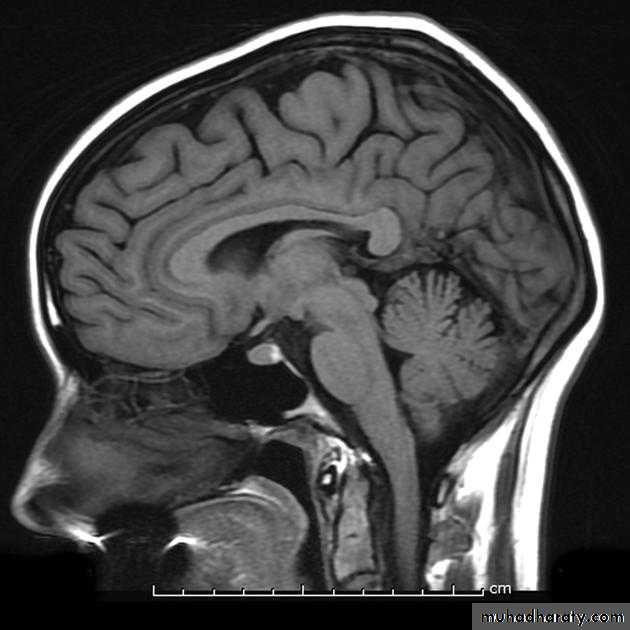

Common CT findings of traumatic brain injury